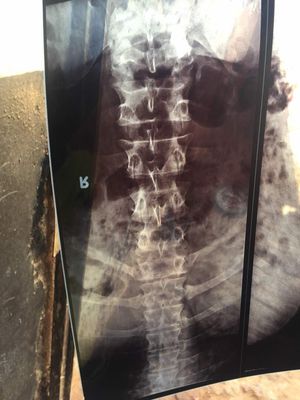

32 yr male what is diagnosis and treatment l5 bones

Turn this xray 180 degree reload Again

I guess that this patient is super human...cus sacrum is upwards and ribs are downwards